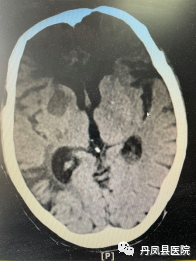

图分别为:溶栓后24小时头颅CT复查无出血;第二天头颅MRI提示右侧基底节区急性脑梗死。